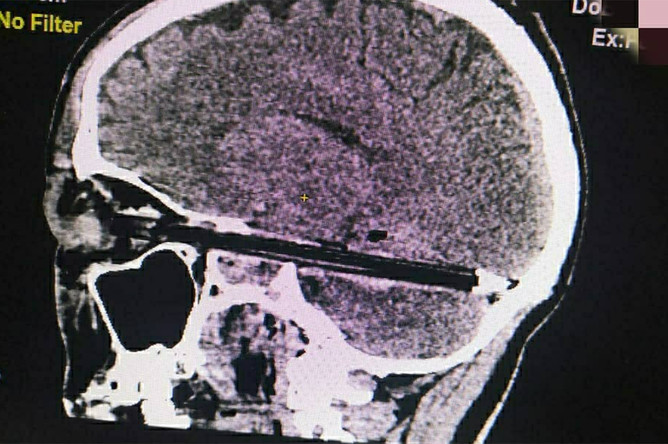

Следователи начали проверку после смерти пациента с шариковой ручкой в голове

Следственный комитет России начал проверку после смерти мужчины, которого госпитализировали из СИЗО Новочеркасска в Ростовской области с ручкой в голове. Об этом сообщает ТАСС со ссылкой на представителя СУСК России по региону.

Согласно информации областного ГУФСИН, 5 февраля 37-летний мужчина получил травму на территории исправительной колонии, где он содержался. Обвиняемый заявил, что травмировал он себя сам, в состоянии нервного срыва.

Впоследствии его экстренно госпитализировали с шариковой ручкой в голове. Ручка повредила ему глаз и вошла в мозг на весь диаметр полости черепа, при этом она прошла в миллиметре от важнейших сосудов и ствола головного мозга. Врачи прооперировали пострадавшего, после чего он был переведен в реанимацию. Во вторник, 9 февраля, стало известно, что пациент скончался.